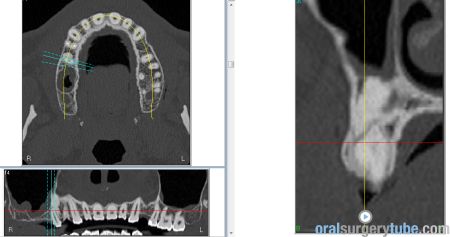

Con este comentario haremos una pausa en el caso hasta que llegue la colocación de los implantes. Por el momento, está todo solucionado. No hay sintomatología alguna, y lo más importante, en TAC realizado el martes 31.07.2018, podemos ver que el seno ha drenado por completo y está aireado. Hasta nuevo aviso, suspendemos todo tipo de medicación. Subimos imágenes del último TAC donde podemos apreciar que hemos perdido algo de xenoinjerto, pero la zona de menor altura aún tiene 10 mm. Podemos ver en una de las imágenes la zona de la ventana por donde el seno drenaba. Esperaremos el tiempo reglamentario para poder reevaluar si el xenoinjerto sigue siendo viable. Ha sido un gran placer contar con este equipo y poder aportar un grano de arena a solucionar complicaciones quirúrgicas.

Respondo a Hernán Rescala: Antes que nada, darte las gracias por tu comentario. Este paciente llevaba dos coronas ferulizadas 1-4; 1-5 cuando le vimos en 2014. En aquel momento, no se hizo ningún tratamiento, y fue una pena. La pieza 16, por la que ha venido toda esta historia era recuperable. Quizás no supimos convencerle de intervenir de inmediato, de lo cual me culpo. Subo panorámica de 2014. Volvió en 2018 con las coronas caídas y el pilar 1-4 totalmente destruido. La pieza 1-5 era vital y colocamos un provisional, el cual descementó varias veces. La 1-4 decidimos mantenerla para hacer un implante cuando colocáramos los demás. El dia de la cirugía del seno, vino con el provisional roto, pero al no tener mucha sensibilidad en la pieza, intervinimos y lo dejamos tal cual. Después de tu observación volvimos a valorar esta pieza el viernes 13 con un test pulpar y Rx, que subo. La pieza sigue vital, con pruebas frio, calor y eléctrica(12 en escala 1-100). Subo TAC previo

Continúo con el seguimiento que vamos dando a este paciente: Visitado el miércoles 11.07.2018. Hay ausencia total de sintmatología. Retiramos el drenaje, hacemos Prueba de Valsalva positiva, pero sale aire y un poco de sangre. Dejamos cicatrizar por segunda intención. Pedimos continuar la medicación antibiótica y solicitamos un TAC. El seno maxilar está ocupado como vemos en la imagen, pero el biomaterial está contenido en la zona injertada: no existe ningún gránulo de xenoinjerto dentro del seno. La apófisis mastoidea está aireada.